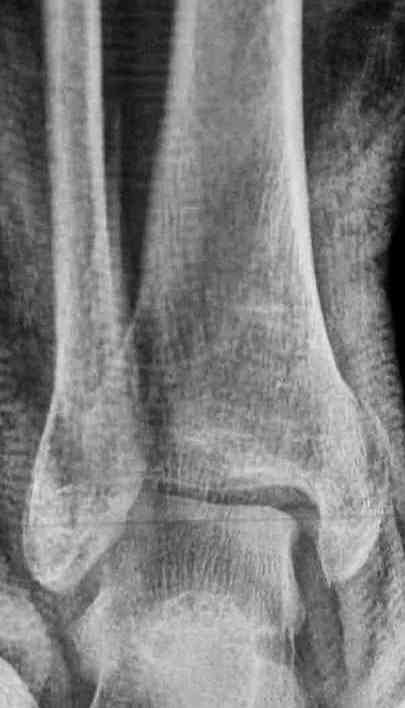

Уже 15 лет в отделении мы активно оперируем свежие переломы ГСС по принципам АО и вполне удовлетворены результатами лечения свежей травмы. В случаях же операций при позднем поступлении или реконструкции после неудачных вмешательств в ряде случаев сохраняется нестабильность ГСС, тенденция к вальгусной деформации. В свежих случаях никогда не приходилось производить шов дельтовидной связки, пластики тоже ни разу не выполнялись. Два примера на снимках.Первый - врач 38 лет, неудачно оперированный в своей больнице с двухлодыжечным переломом, разрывом МБС был повторно оперирован через 8 месяцев. Пытались восстановить длину наружной лодыжки остеотомией, освежили МБС, два месяца функционального лечения без нагрузки на стопу.Сейчас ходит с легкой хромотой, устает к обеду, вальгусное отклонение стопы корригировано супинатором. На Рграммах видны дистрофические изменения латерального эпифиза большеберцовой кости. Первый снимок через 6 месяцев после травмы, операции остеосинтеза болтом-стяжкой, удаленной по причине нестабильности и наличия свища над металлом. Второй снимок через 3 месяца после реконструктивной операции.

Вторая пациентка 34 лет, перелом получала в Испании, где от операции отказалась, дома по приезду сняла скотчкаст и лечилась у костоправов, нагрузка с 3 недели. Операция через 3 мес после травмы. Остеотомия м-б кости, фиксация пластиной, восстановление МБС. Так как медиальная лодыжка подтянулась, суставная щель на ЭОП контроле нормализовалась ограничились латеральным доступом. Реконструкцию заднего края не пытались сделать тк там уже прослеживалась консолидация, а сминать эпиметафиз не хотелось. В настоящее время ходит с тростью \три месяца после операции\, сустав нестабилен-слабость дельтовидной связки. Супинатор и плотные кроссовки дают возможность длительно ходить. Первый снимок сделан в Испании после репозиции, второй через 2 месяца после травмы перед операцией, третий-через 3 мес после операции.

Глубокоуважаемый Антон, мне кажется в обоих наблюдениях не была достигнута цель операции: Восстановление длины малоберцовой кости и и фиксация ее в анатомичном положении. Отсюда все последующие проблемы, а не от дельтовидной связки.

Как отметили коллеги, в обоих наблюдениях не были достигнуты цели восстановления, игнорирован основной принцип, длина малоберцовой, без которой всякие попытки обрешены на провал.

По снимкам в первом случае, укорочение малоберцовой приблизительно около 8-10 мм. Удовлетворительным восстановлением длины малоберцовой считается, когда на снимке суставная щель равны со всех сторон.